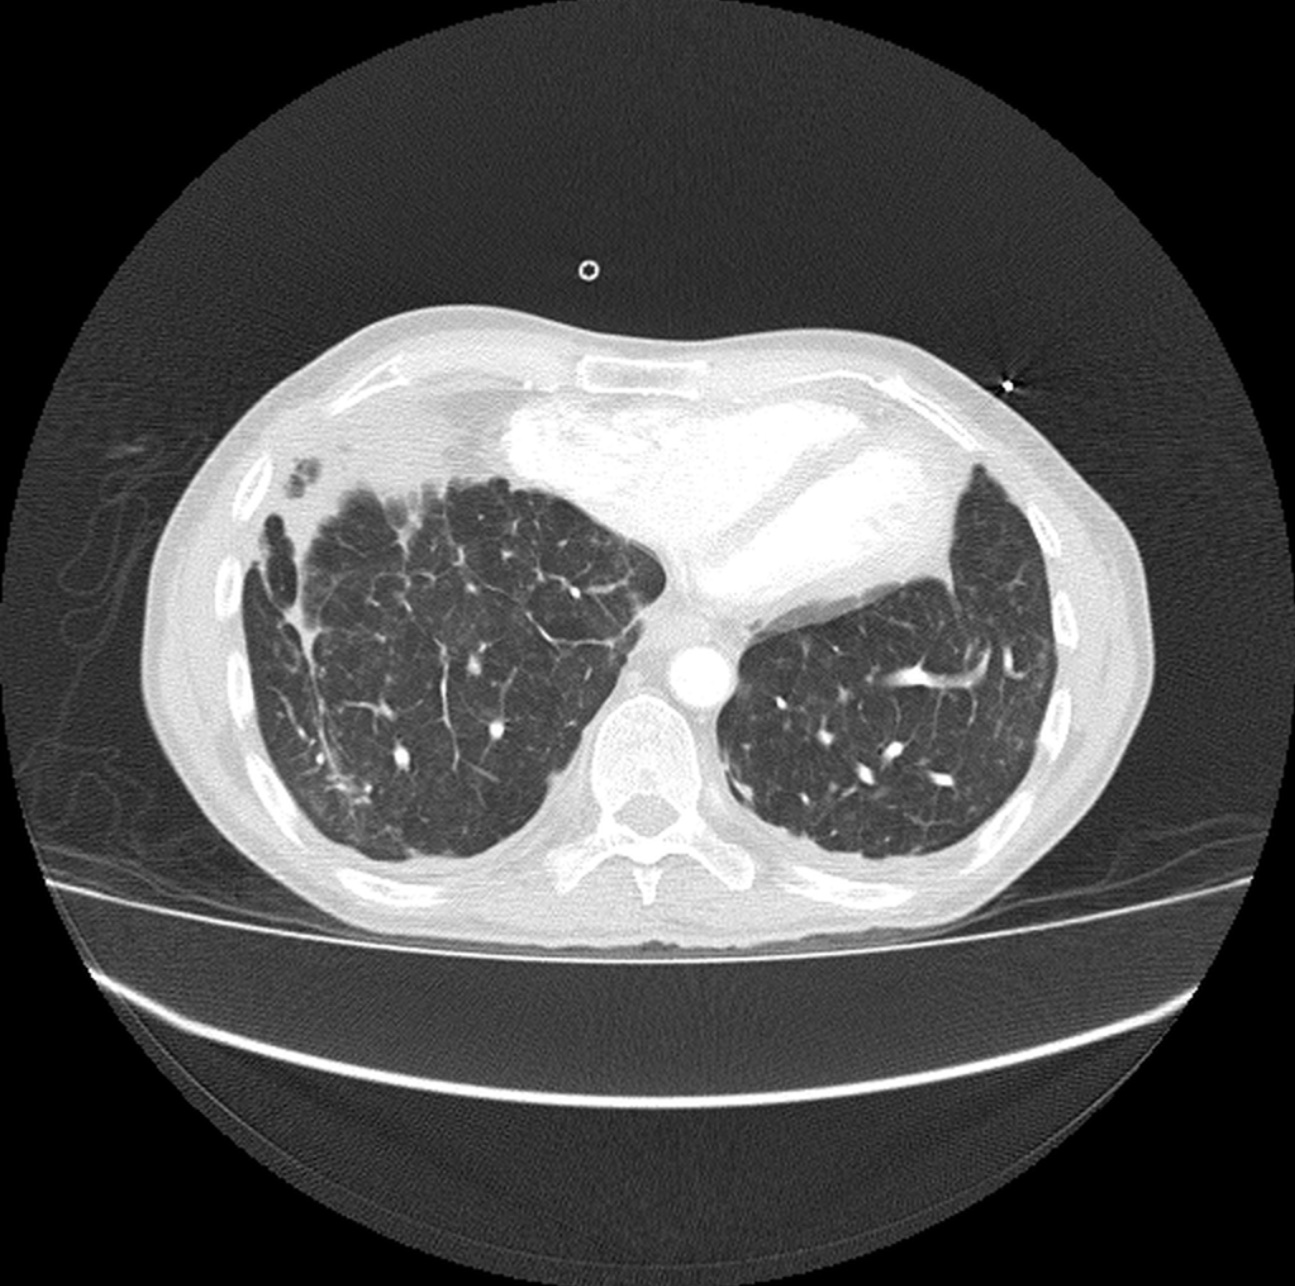

Hombre de 61 años asintomático. Colonoscopia demuestra válvula ileocecal ulcerada y estenótica. No hay antecedente de Enfermedad Inflamatoria Intestinal.

Con base en lo anterior el siguiente paso a seguir es?

a) Valoración por cirugía general.

b) Iniciar tratamiento con anti-inflamatorios e inmunosupresores.

c) Biopsia bajo guía ecográfica de las lesiones focales hepáticas.

d) Repetir colonoscopia.